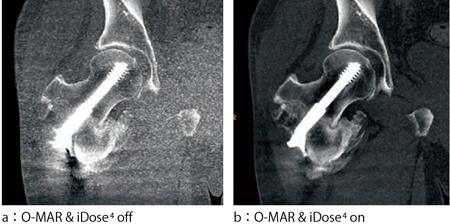

さらに,O-MARは,それ自身も逐次近似を応用した再構成法となるが,フィリップスにおけるもう1つの逐次近似応用再構成法であるiDose4と組み合わせて使用することが可能である(図7)。これにより,金属の含まれた被検者においても,逐次近似応用再構成の利点である低被ばく検査や,さらなる高画質検査,低電圧撮影を使用した低造影剤量の検査など,近年のCT機能の向上を最大限活用することが可能である。

図7 O-MAR & iDose4併用画像例